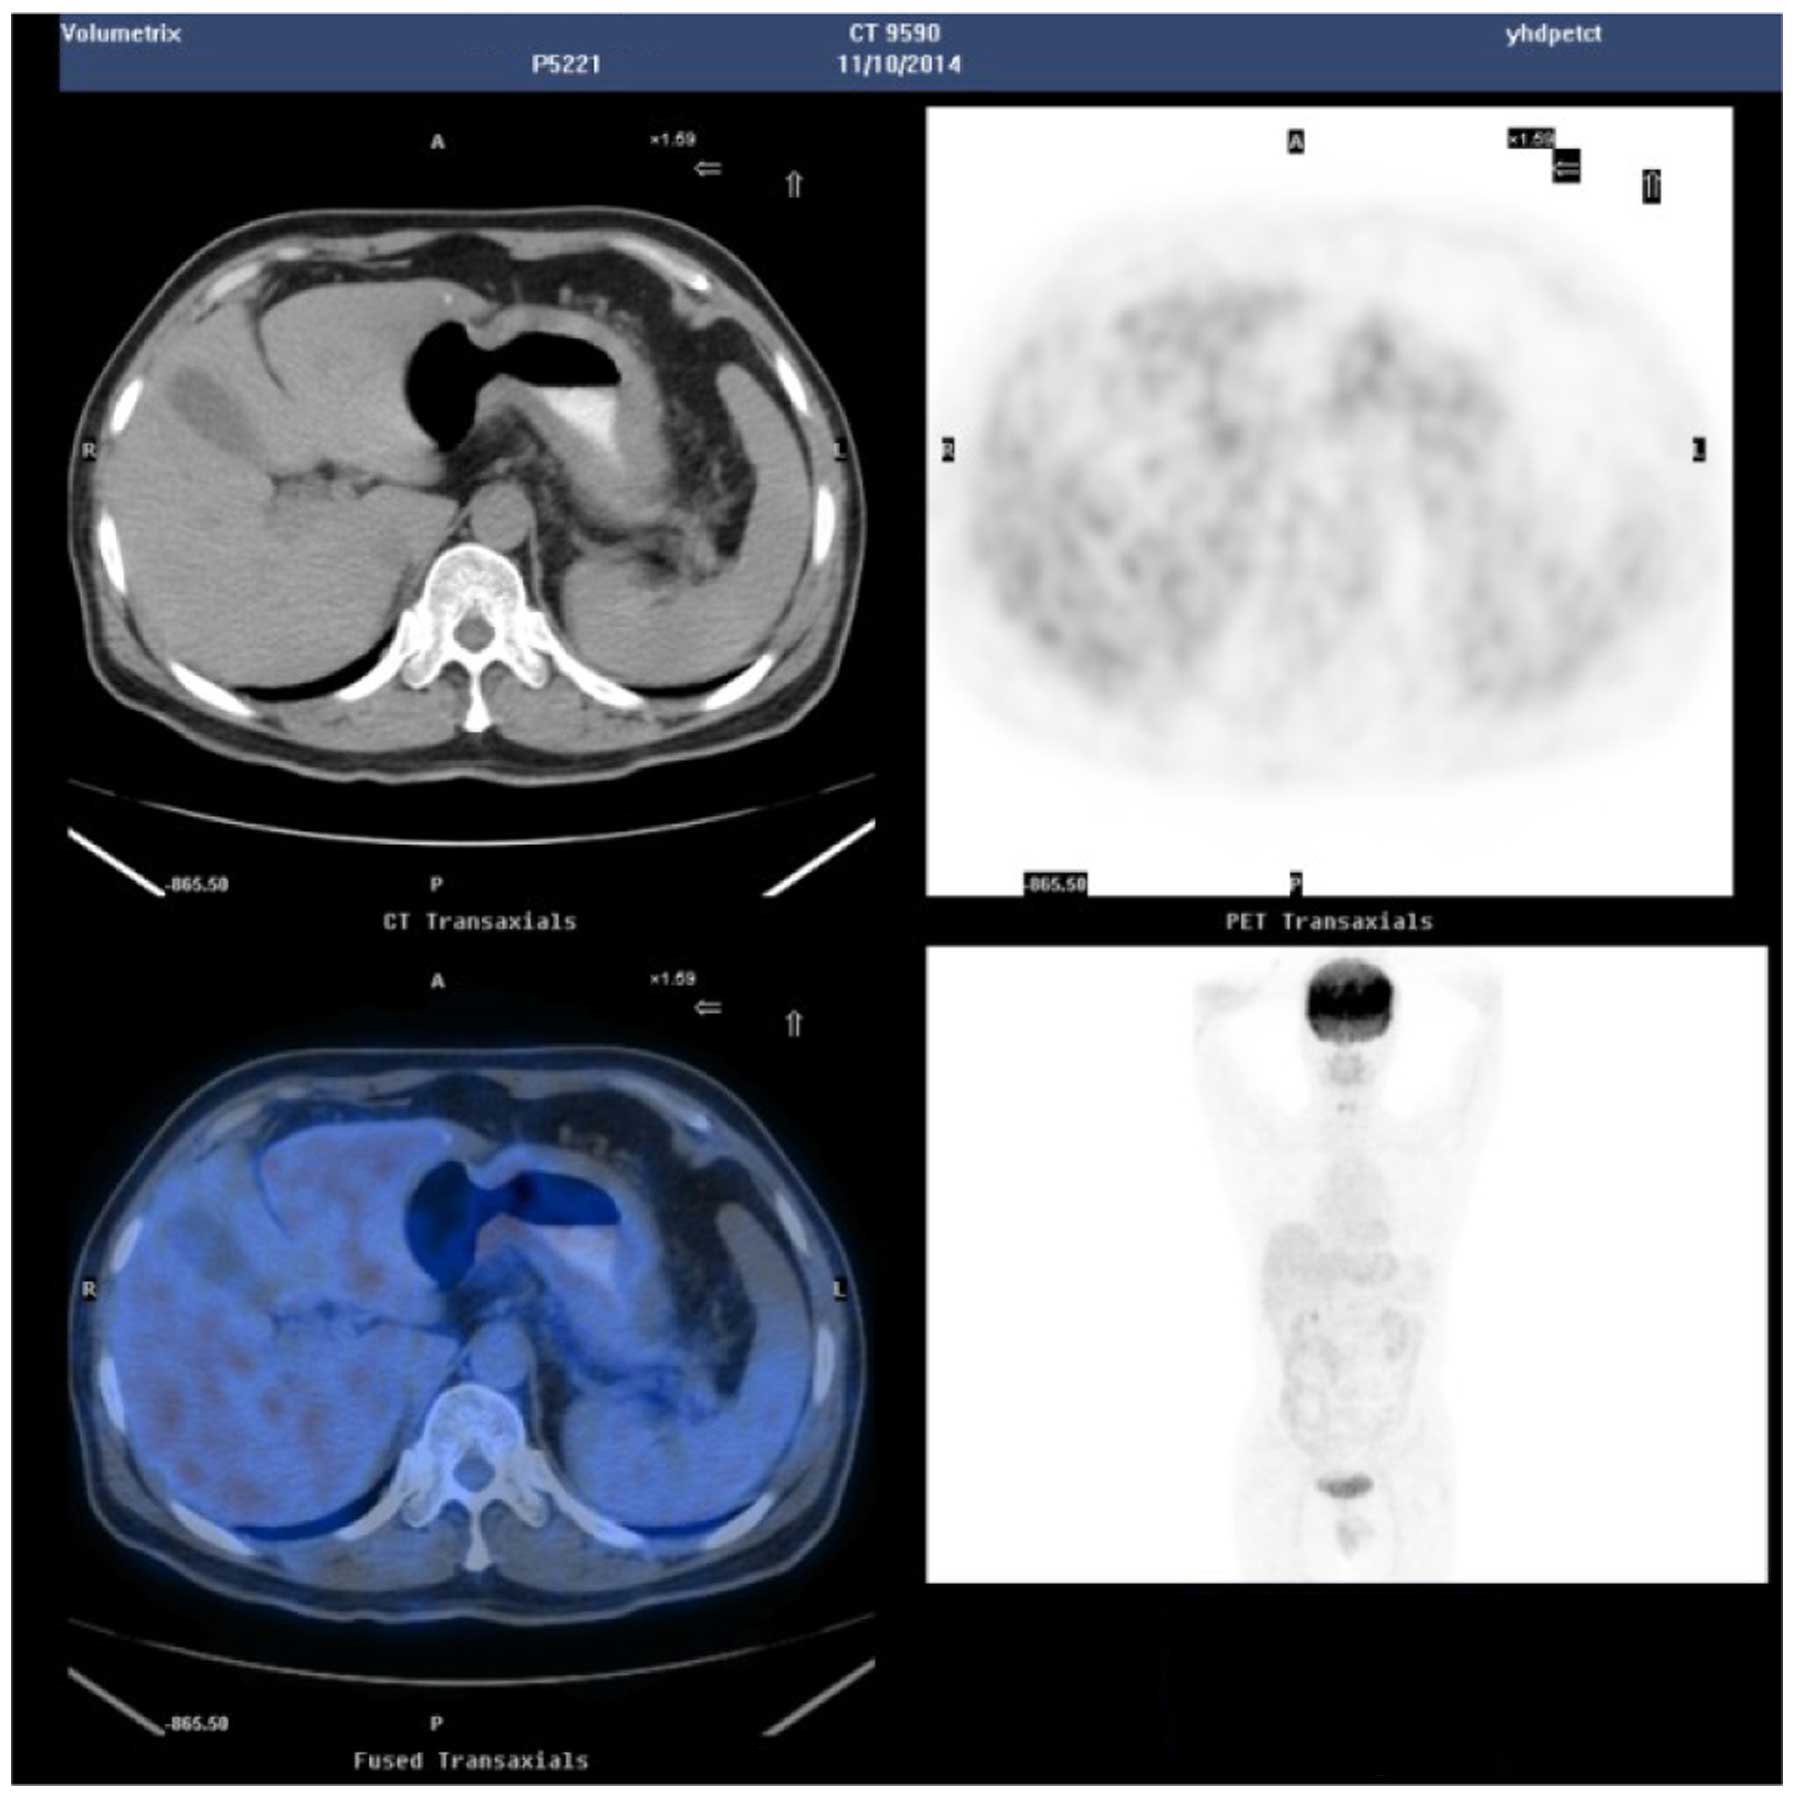

Pet Ct Scan Showing The Gastric Lesion In The Cardia Download Scientific Diagram

You have a pet ct scan to find out more about where exactly your stomach cancer is and whether it has spread. At left is a ct scan while the center image is from a pet scanner. With cancer cells they appear as bright spots due to its higher metabolic rate compared to normal cells.

Get the most precise diagnosis with pet ct pet ct technology shows biological activity within organs and can therefore detect cancer in the earliest stages. Gastric cancer is a leading cause of cancer death worldwide. The image on the right is a combined ct pet scan.

The bright spot in the chest seen best on the pet and ct pet scans is lung cancer.